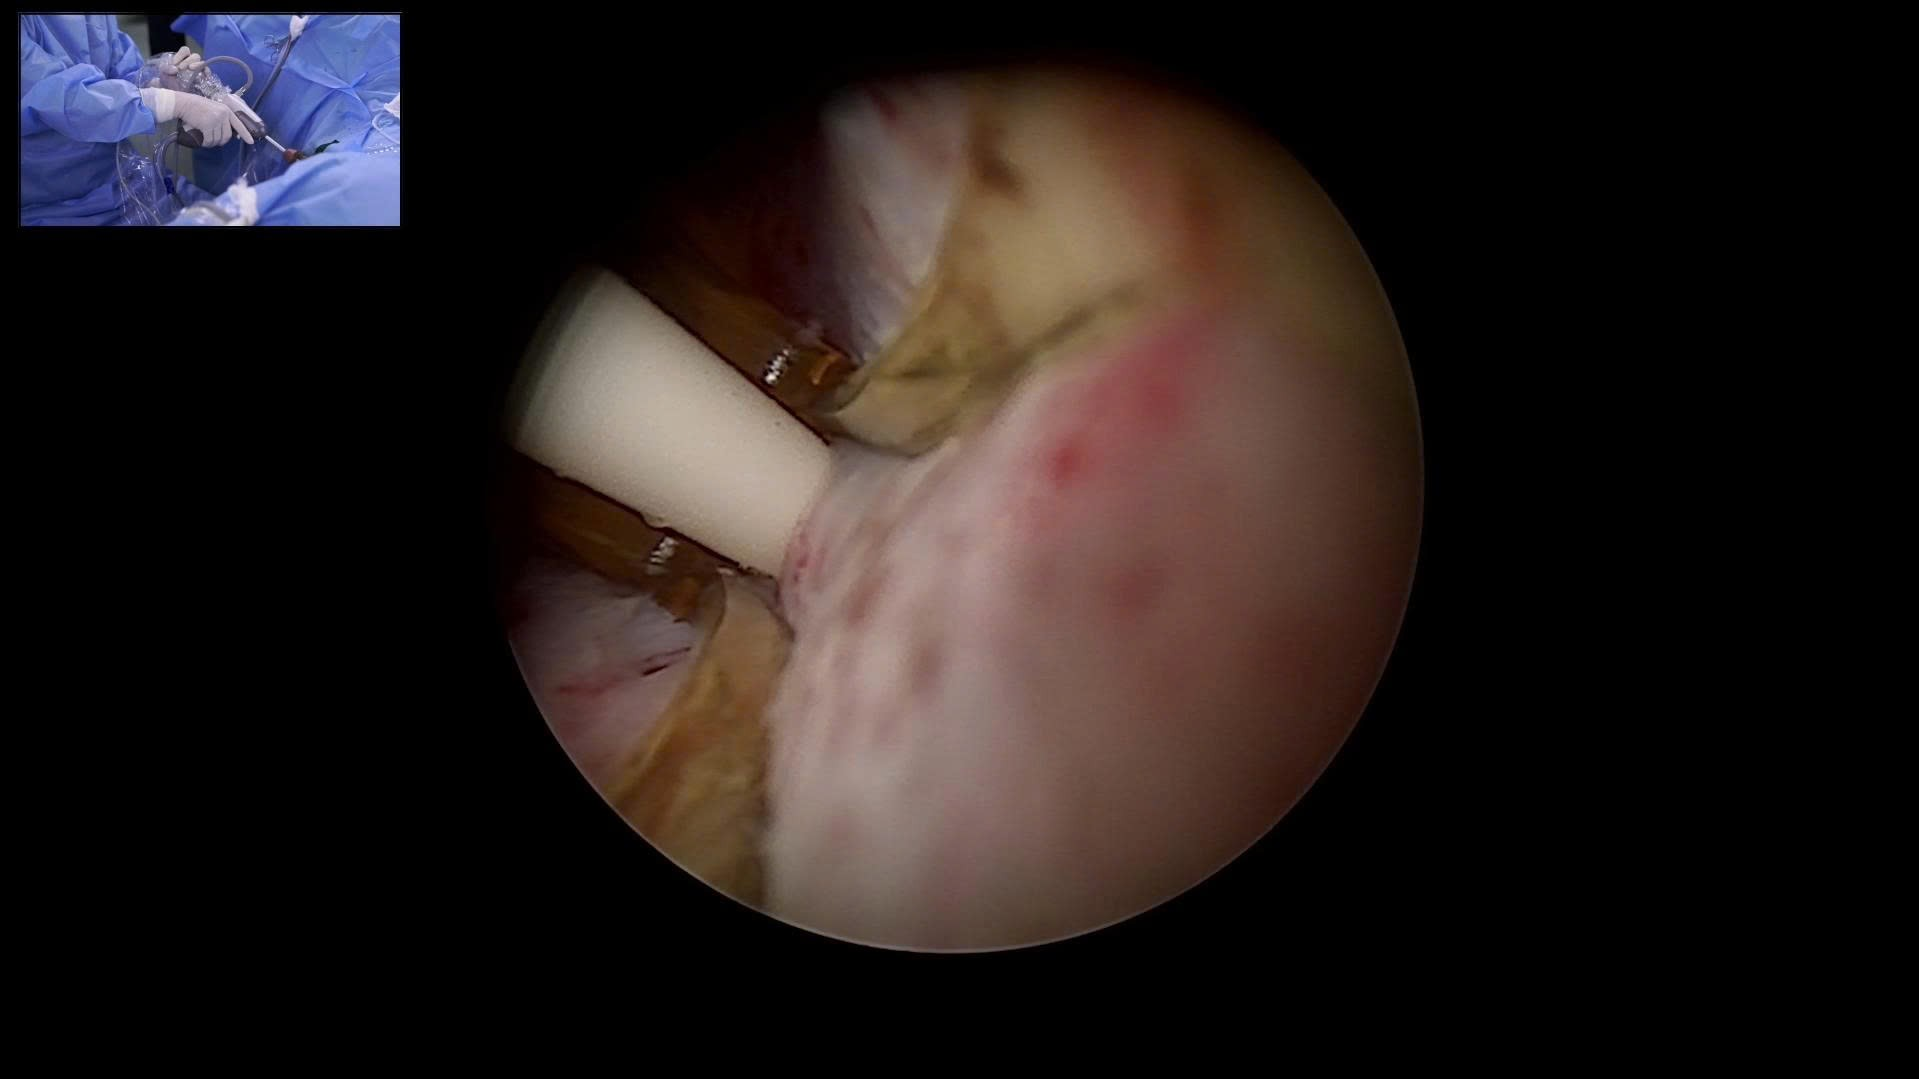

Hình ảnh: Nội soi trong quá trình thực hiện liệu pháp nhiệt hơi nước (Rezūm) tại Bệnh viện Bạch Mai

Cơ chế Độc đáo: Kỹ thuật sử dụng năng lượng nhiệt từ hơi nước ở khoảng 103°C. Hơi nước được đưa chính xác vào mô tuyến tiền liệt phì đại, phá hủy có chọn lọc phần mô bệnh mà không cần cắt bỏ. Mô hoại tử sẽ được cơ thể hấp thu tự nhiên theo thời gian, giúp giải phóng tắc nghẽn và cải thiện dòng tiểu.